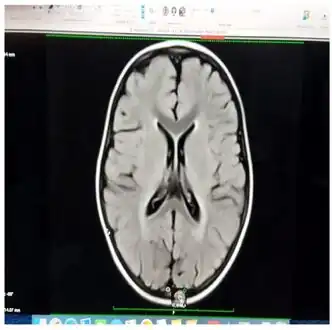

The diagnosis of Pelizaeus–Merzbacher disease is often first suggested after identification by magnetic resonance imaging of abnormal white matter (high T2 signal intensity, i.e. T2 lengthening) throughout the brain, which is typically evident by about 1 year of age, but more subtle abnormalities should be evident during infancy.

Iso intensity in bilateral periventricular deep white matter

Iso intensity in bilateral periventricular deep white matter Left- MRI,abnormal high signal internal capsule,Right MRI,high signal white matter of cerebellum